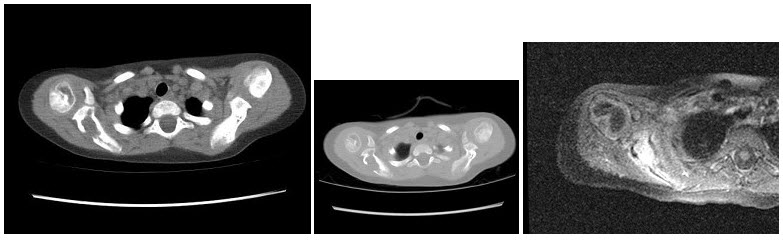

8、单项选择题

根据图像,该病例最不可能的诊断为()

11、单项选择题

女,2岁半,无痛性右肩部肿块,结合图像,最可能的诊断是()